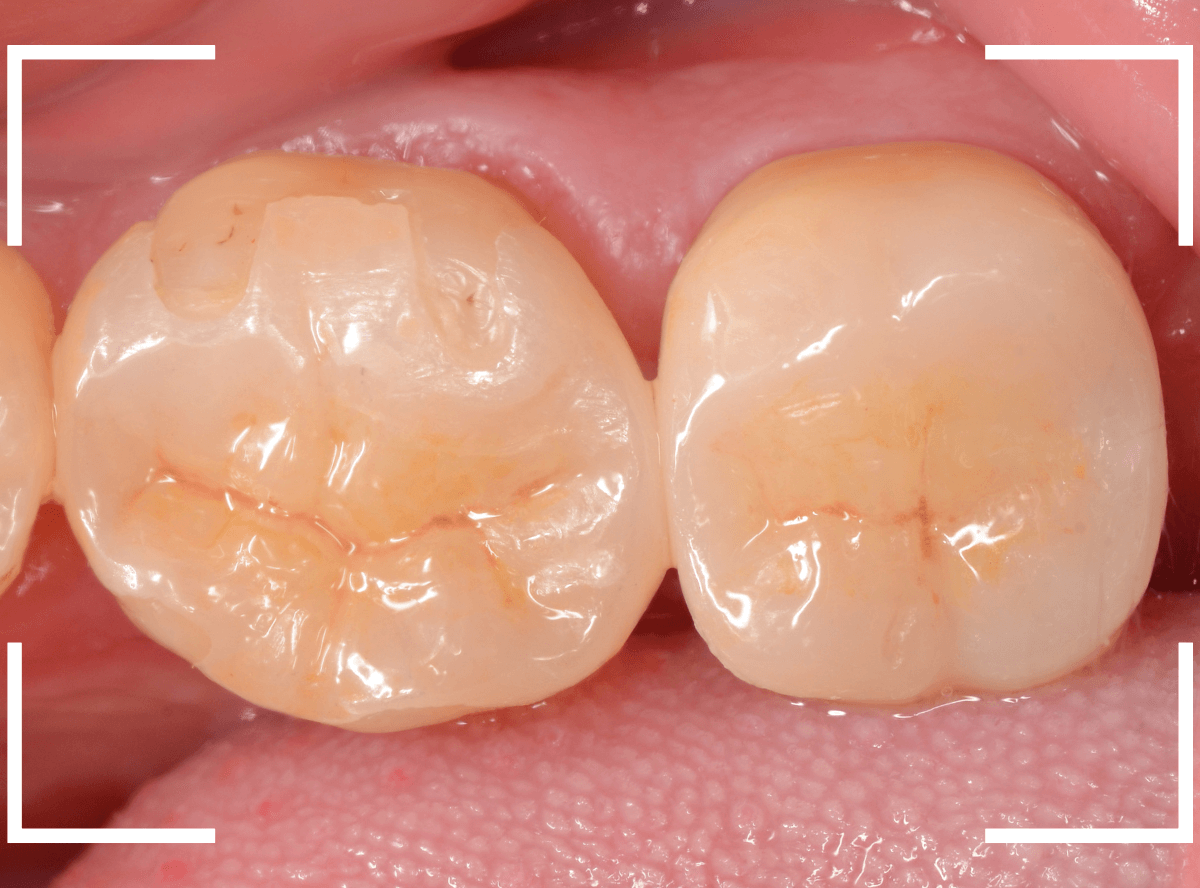

set後の写真です。

患者さんにも満足していただける仕上がりになりました。

治療前後の写真になります。

やはり、印象が大きく変わりますね。